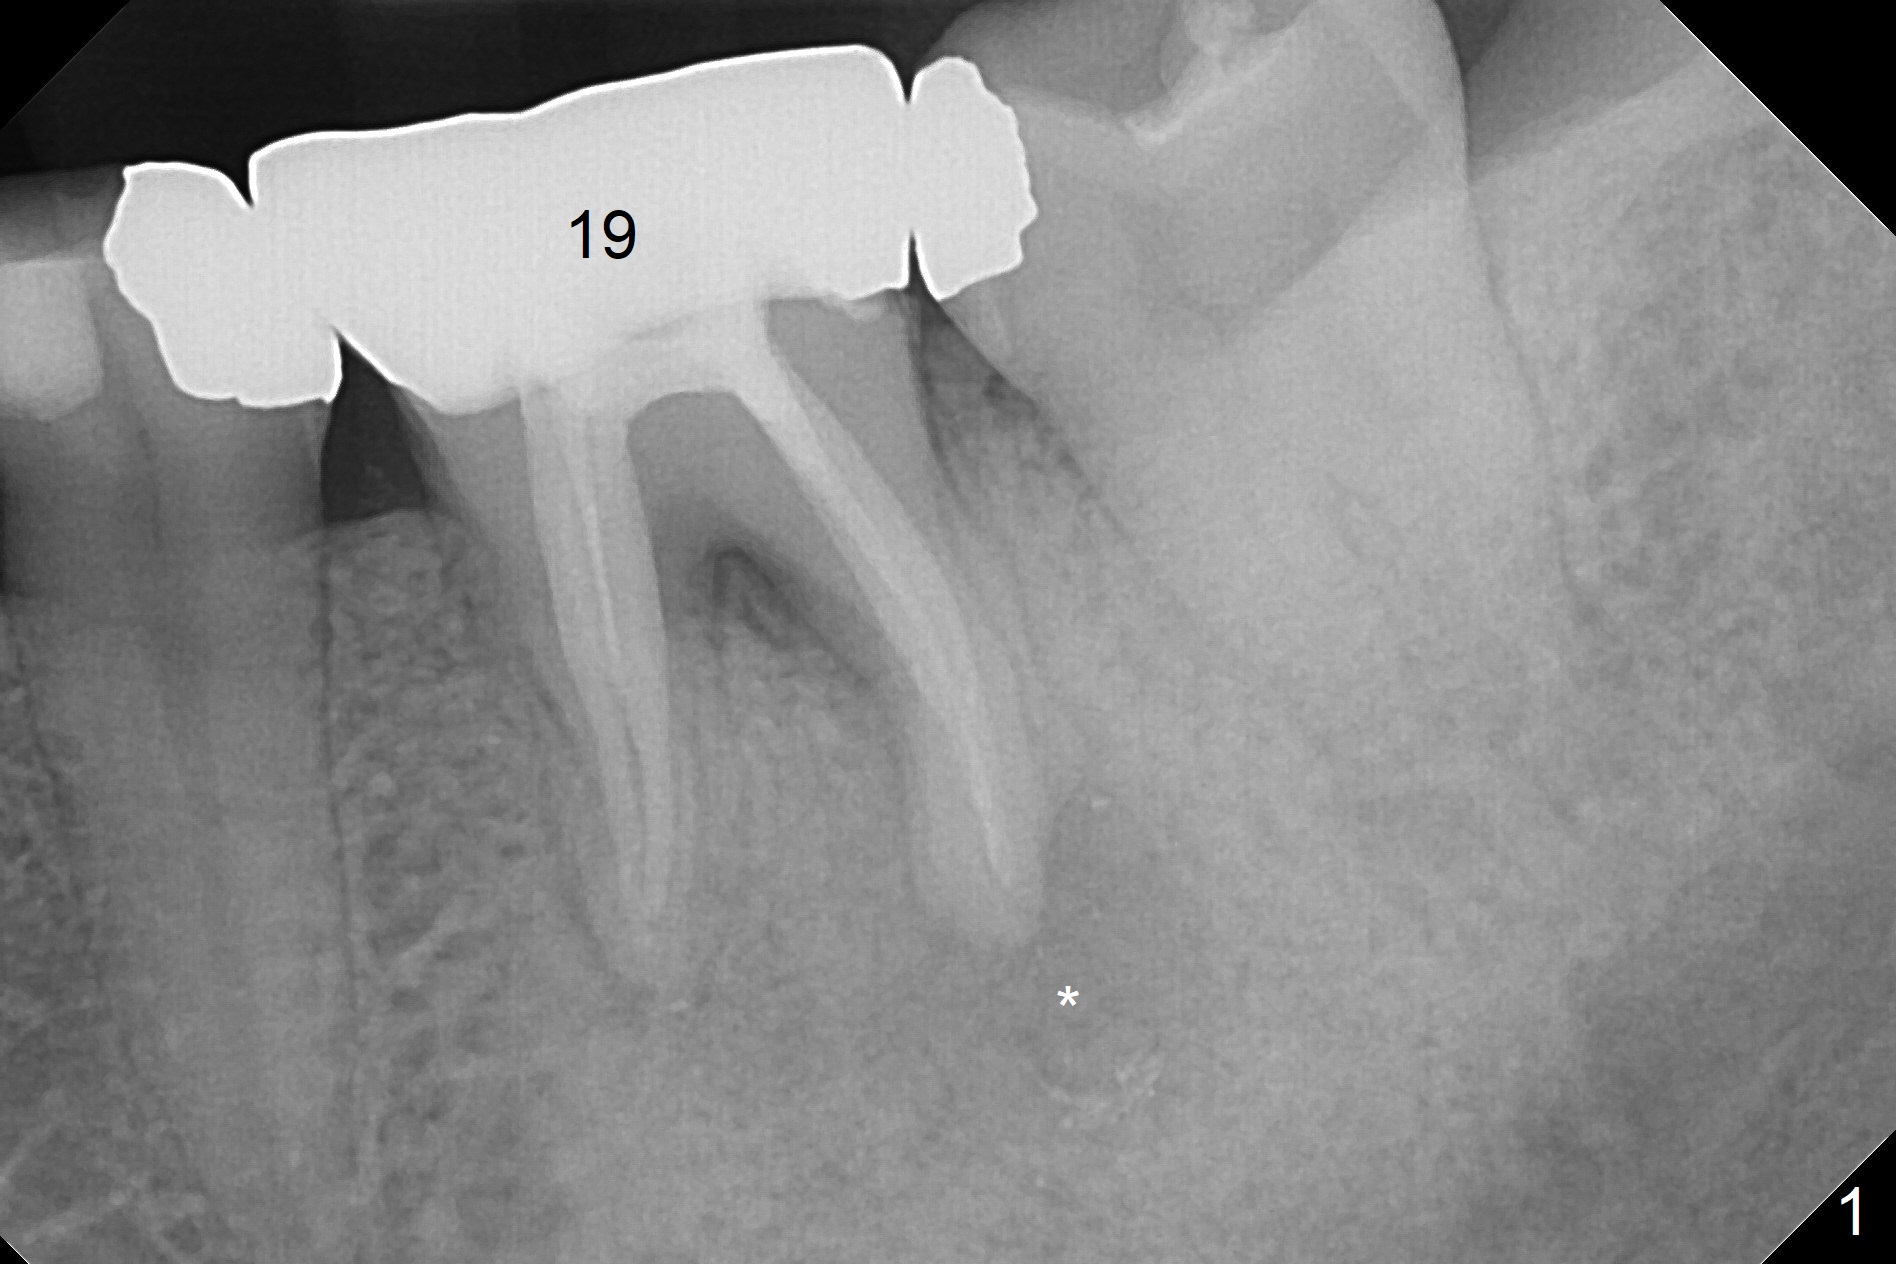

A 53-year-old woman has discomfort at #19 4-5 years post RCT (Fig.1 (*: PARL), 1 year before extraction). She returns for implant placement 4 months post socket preservation in other office (Fig.2 *). The socket appears to have healed with dense bone formation (average 1160 units, Fig.3). A 5x11.5 mm implant will be placed with guide (Fig.4). Will composite at #20 MOL (Fig.2 arrowhead) and PVS impression after CBCT affect surgical guide fabrication accuracy? Or the composite should be done after guided surgery?